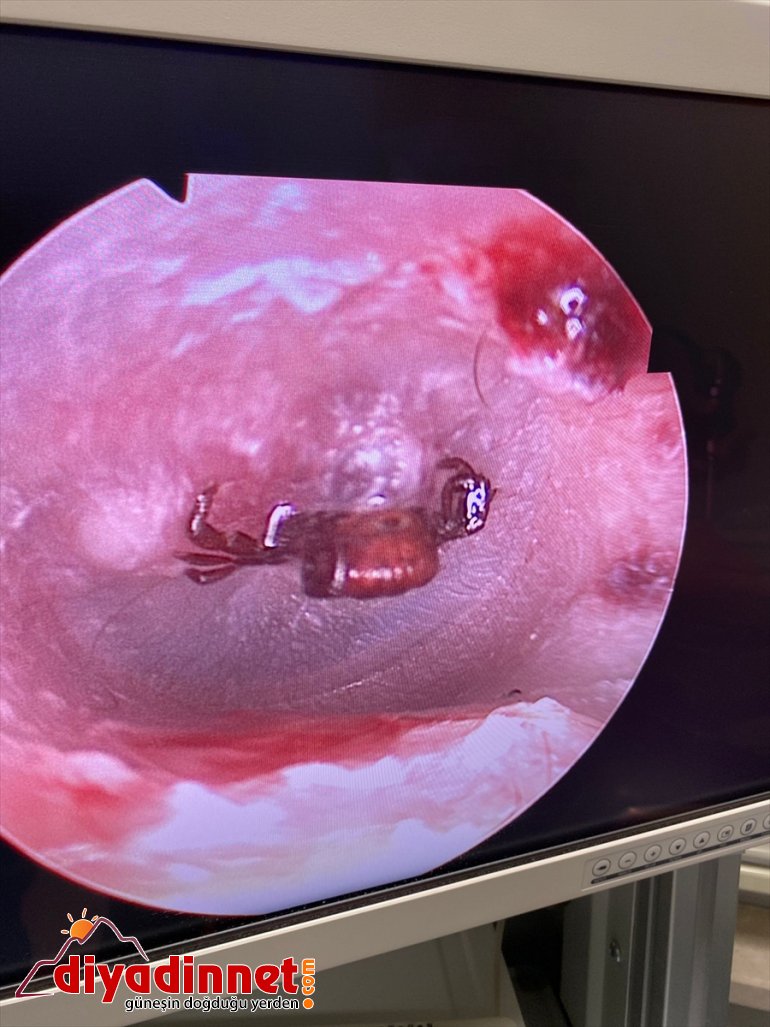

Burada yapılan tetkiklerde, kadının kulak zarına kene yapıştığı tespit edildi. Kulak burun boğaz doktoru Samet Ağcayazı'nın müdahalesiyle kene bulunduğu yerden çıkarıldı.

Vakanın çok sık rastlanan bir durum olmadığını ifade eden Ağcayazı, "Kulak zarına yapışmış keneyi gördük. Endoskopi kamera yardımıyla da keneyi çıkardık. İlk kez kulak zarına yapışmış bir kene gördük." diye konuştu.

Ağcayazı, kulak zarının yapı itibarıyla deri gibi mukavemetli olmadığı için keneyi kolay çıkardıklarını dile getirdi.